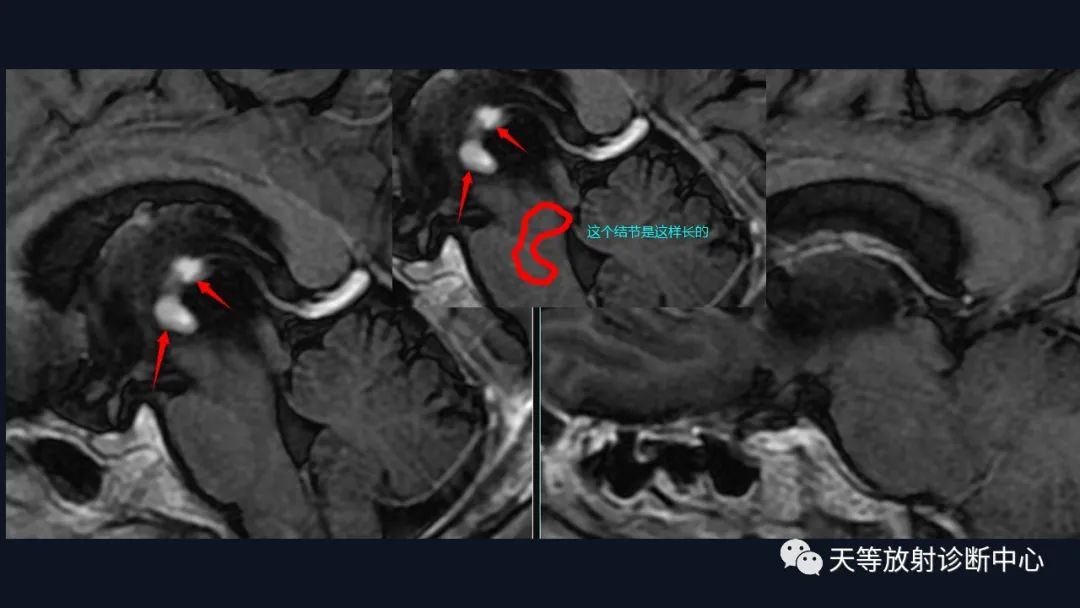

1、刀切征

3、尖角征

6、形态上怪异